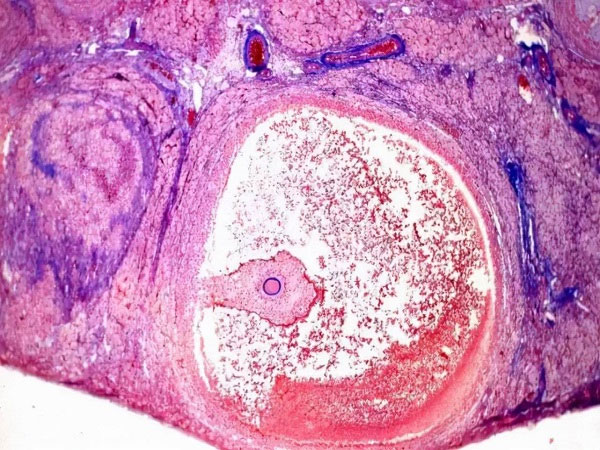

大家都知道,卵巢是女性生育和保持青春的重要器官,同时承担着分泌体内重要激素的作用。在女性的卵巢中有成千上万的卵泡,在不同的时期中卵泡会不断的生长发育直到成熟。正常情况下,女性卵巢中的卵泡数量应该是5-12个左右,过多过少的卵泡都会对女性的身体健康和生育造成影响,卵巢中只有两个卵泡是不正常的,有卵巢早衰的风险,建议及时进行治疗。

众所周知,女性卵巢中的卵泡数量会随着年龄的不断增长而变化,女性的年龄越大卵巢功能就越差,卵泡的数量也会随之减少。针对育龄期的女性来说,单侧卵巢中的卵泡数量应该是在3-11个左右的,低于3个或者是高于11个的就都属于异常情况。如果卵巢中只有两个卵泡的话也是不正常的,需要及时进行检查和治疗。不同阶段的女性卵巢中的卵泡数量是不同的,下面就为大家详细介绍一下。